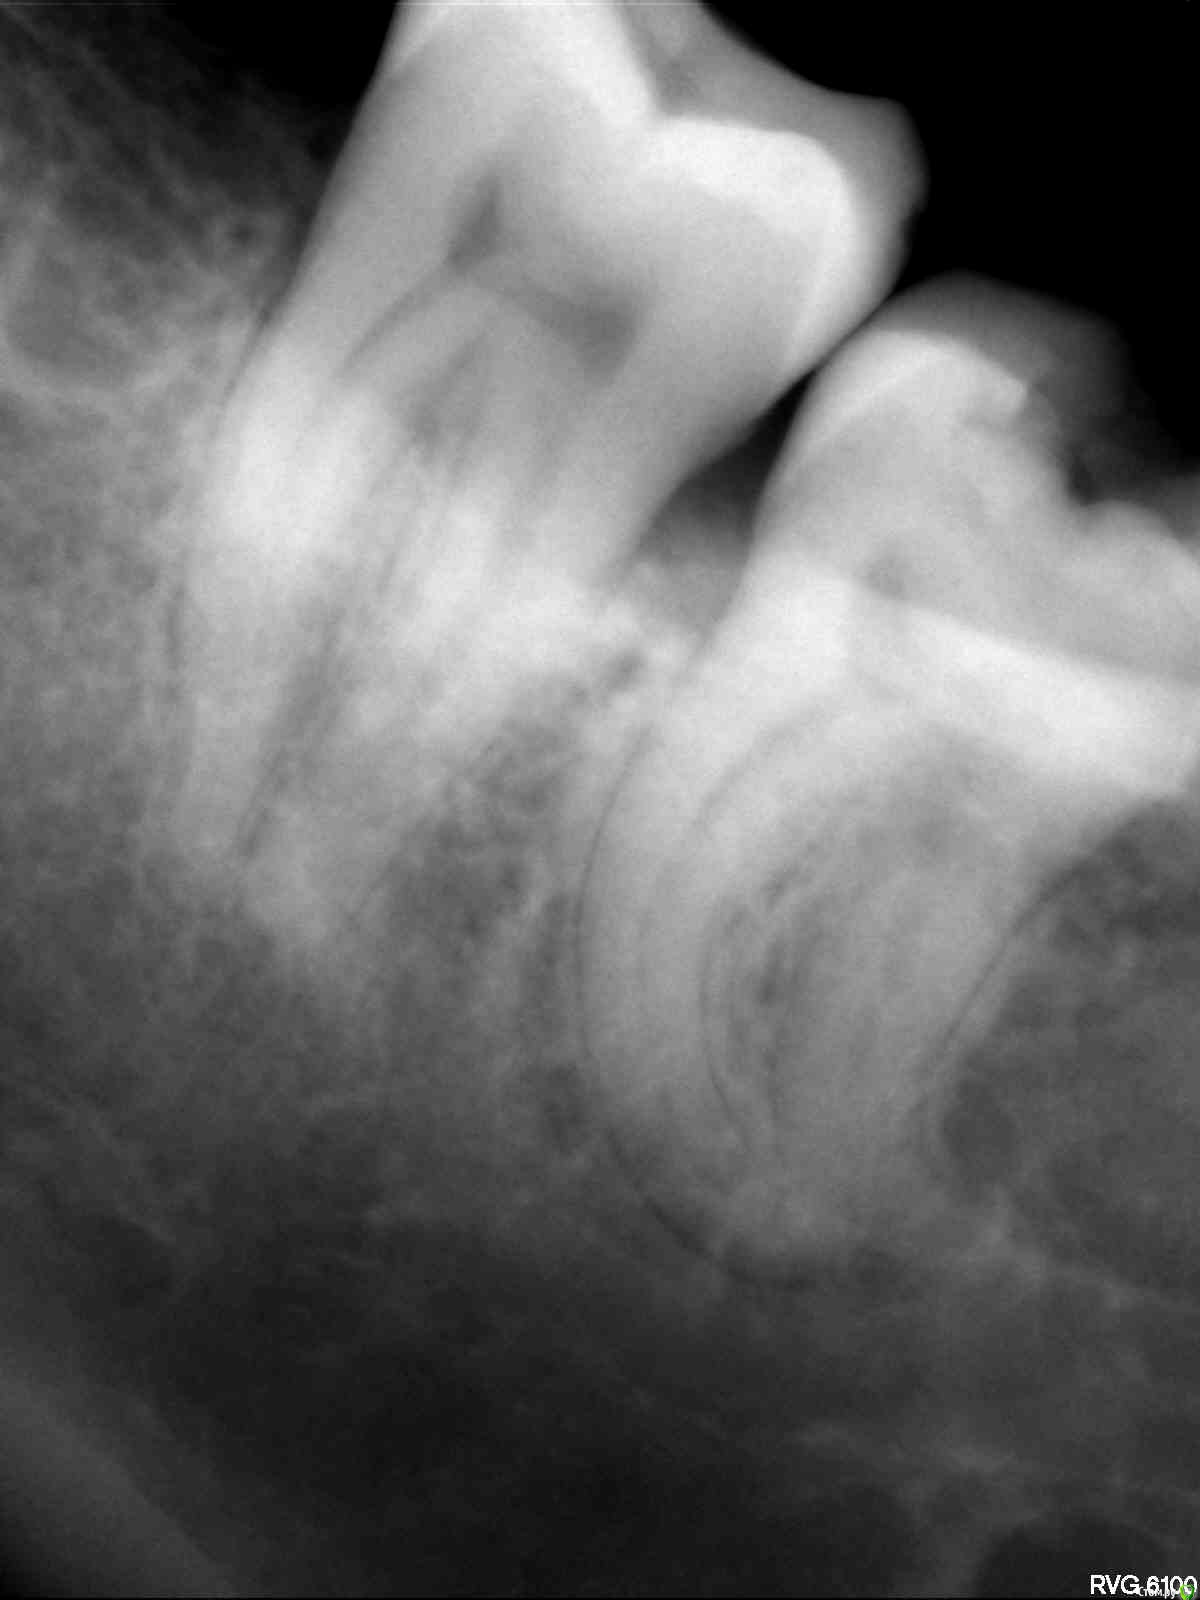

Витторио Орлионе Опубликовано 24 июня, 2015 Поделиться Опубликовано 24 июня, 2015 Уважаемые коллеги, очень нужен ваш мудрый совет. Пациентка обратилась в клинику 23.06 с жалобами на пульсирующие боли в области нижней челюсти слева. На окклюзионной поверхности зуба 3.8 глубокая кариозная полость не сообщающаяся с полостью зуба. Зондирование болезненно, температурная проба положительная, перкуссия слабо болезненна. Пациентка хотела сохранить зуб. Поэтому анестезия, некрэктомия, раскрытие и формирование полости, обработка ручными и mtwo файлами, мыл гипохлоритом. Итог: патенси нет, обломок инструмента, пульпевит №3, септопак. Явка 25.06. Если лечить то:Сообщать ли пациентке об обломке?Какую тактику выбрать (вести на каласепте или отмыть и запломбировать, стоит ли пытаться достать)?Чем пломбировать каналы (гуттаперча или резорцин)? Если удалять то?Как обосновать пациентке смену лечения на удаление?Разделять корни или нет? Ссылка на комментарий

Витторио Орлионе Опубликовано 24 июня, 2015 Автор Поделиться Опубликовано 24 июня, 2015 да, первый эндокосяк, пульпу убрал и пару раз промыл, полом полез 10.02 mtwo и устроил фото сессию.В этот раз без коффера работал, далеко очень, вот и не стал использовать. Ссылка на комментарий

Гарриевич Опубликовано 24 июня, 2015 Поделиться Опубликовано 24 июня, 2015 Как есть так и подайте, зуб 8-ой по ААЭ это запредельная сложность, сломать там инструмент это конечно не приятно, но предсказуемоКак сказал Ico, мойте, мойте, мойте и пакуйте. Резорцин ни к чемуЕсли сломали 10ку то можете в принципе полчаса потратить и постараться его обойти. Главное не пытайтесь это сделать ротари Ссылка на комментарий